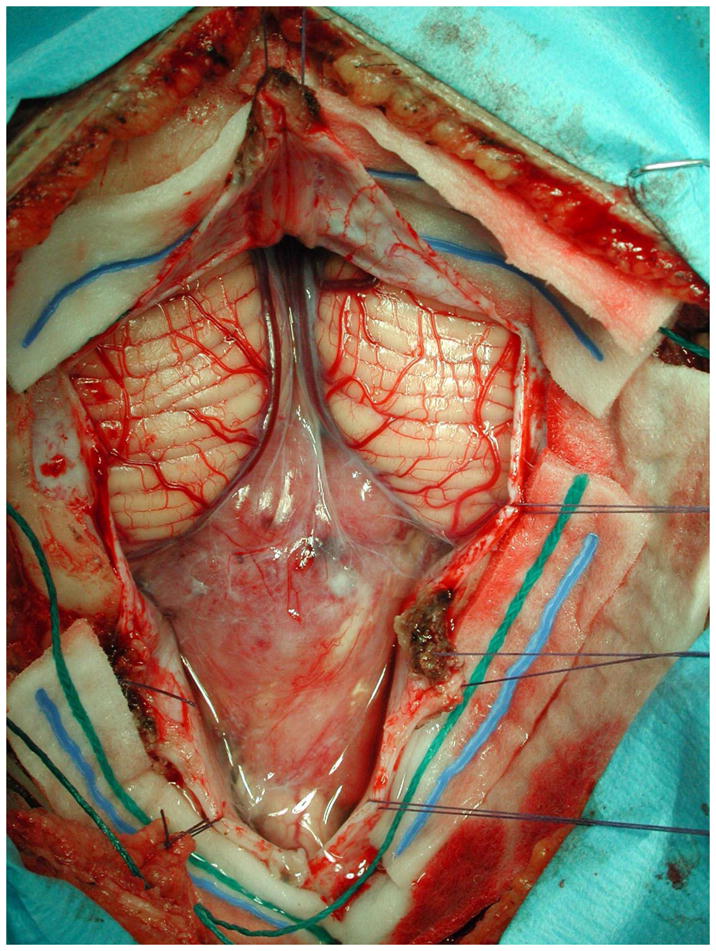

颅后窝室管膜瘤的术中显微照片。肿瘤下降到小脑扁桃体下方,并延伸到颈高椎管。室管膜瘤的目标是在可能的情况下进行手术全切。